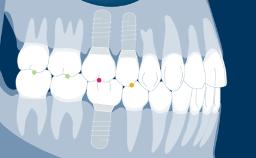

无论治疗的位置或程度如何,种植治疗计划应始终以修复为导向。这可确保种植体植入满足义齿的需求,并与期望的最终效果相一致。为了实现最佳的效果,修复计划应包括:考量所有相关修复因素,并进行适当的诊断检查,在此基础上制定种植义齿和支持种植体的具体计划。

- 讨论与种植治疗相关的修复计划的一般考量因素

- 概述种植义齿及其支持种植体的具体治疗计划要点